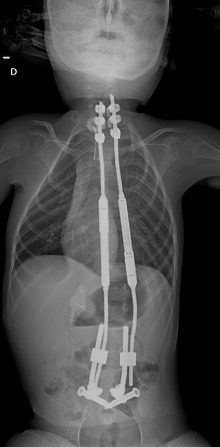

Seule solution pour soulager le petit garçon et freiner l’évolution de sa scoliose : l’implantation de vis dans son bassin et de crochets dans la partie supérieure de sa colonne vertébrale. Ces tiges en métal doivent suivre la croissance de l’enfant et ne bloquent pas les vertèbres qui peuvent encore grandir, a expliqué le CHU dans un communiqué.

Source : Radiographie de Louis, CHU d'Amiens-Picardie

« Leur pose à proximité des racines nerveuses reste très complexe et rare ; elles sont volumineuses au regard de la petite taille des os de l’enfant (vis de 7mm de diamètre à poser dans un couloir osseux de 8mm) », a ajouté l’établissement. L’utilisation du robot a permis aux chirurgiens de réduire le temps de l’intervention et la taille des incisions.